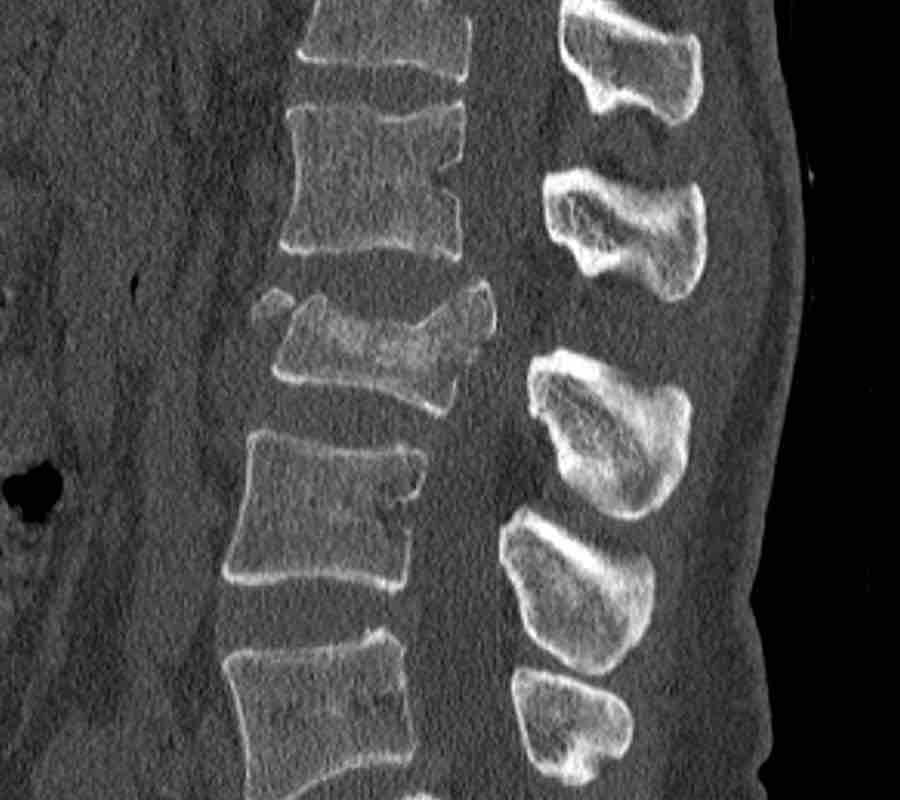

What is the AO-type of the vertebral body fracture based on only these two inages?

Findings:

- Fractures of the vertebral body with involvement of upper endplates (1 points) and posterior wall (2 points)

- Bulging of the posterior wall without any other signs of dislocation is the result of the burst fracture.

Therefore no C injury.

Conclusion

Injury type A3